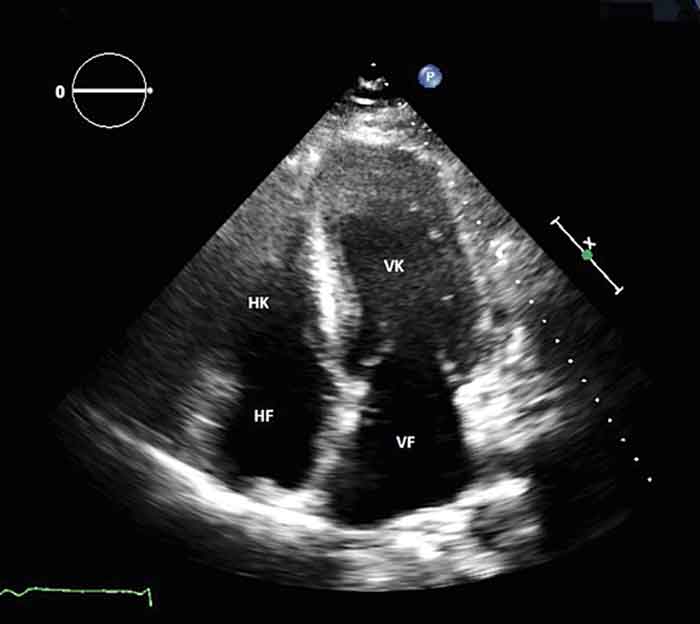

Fallbeskrivning Hypertroft myokardium och låga–normala QRS-komplex är karakteristiskt